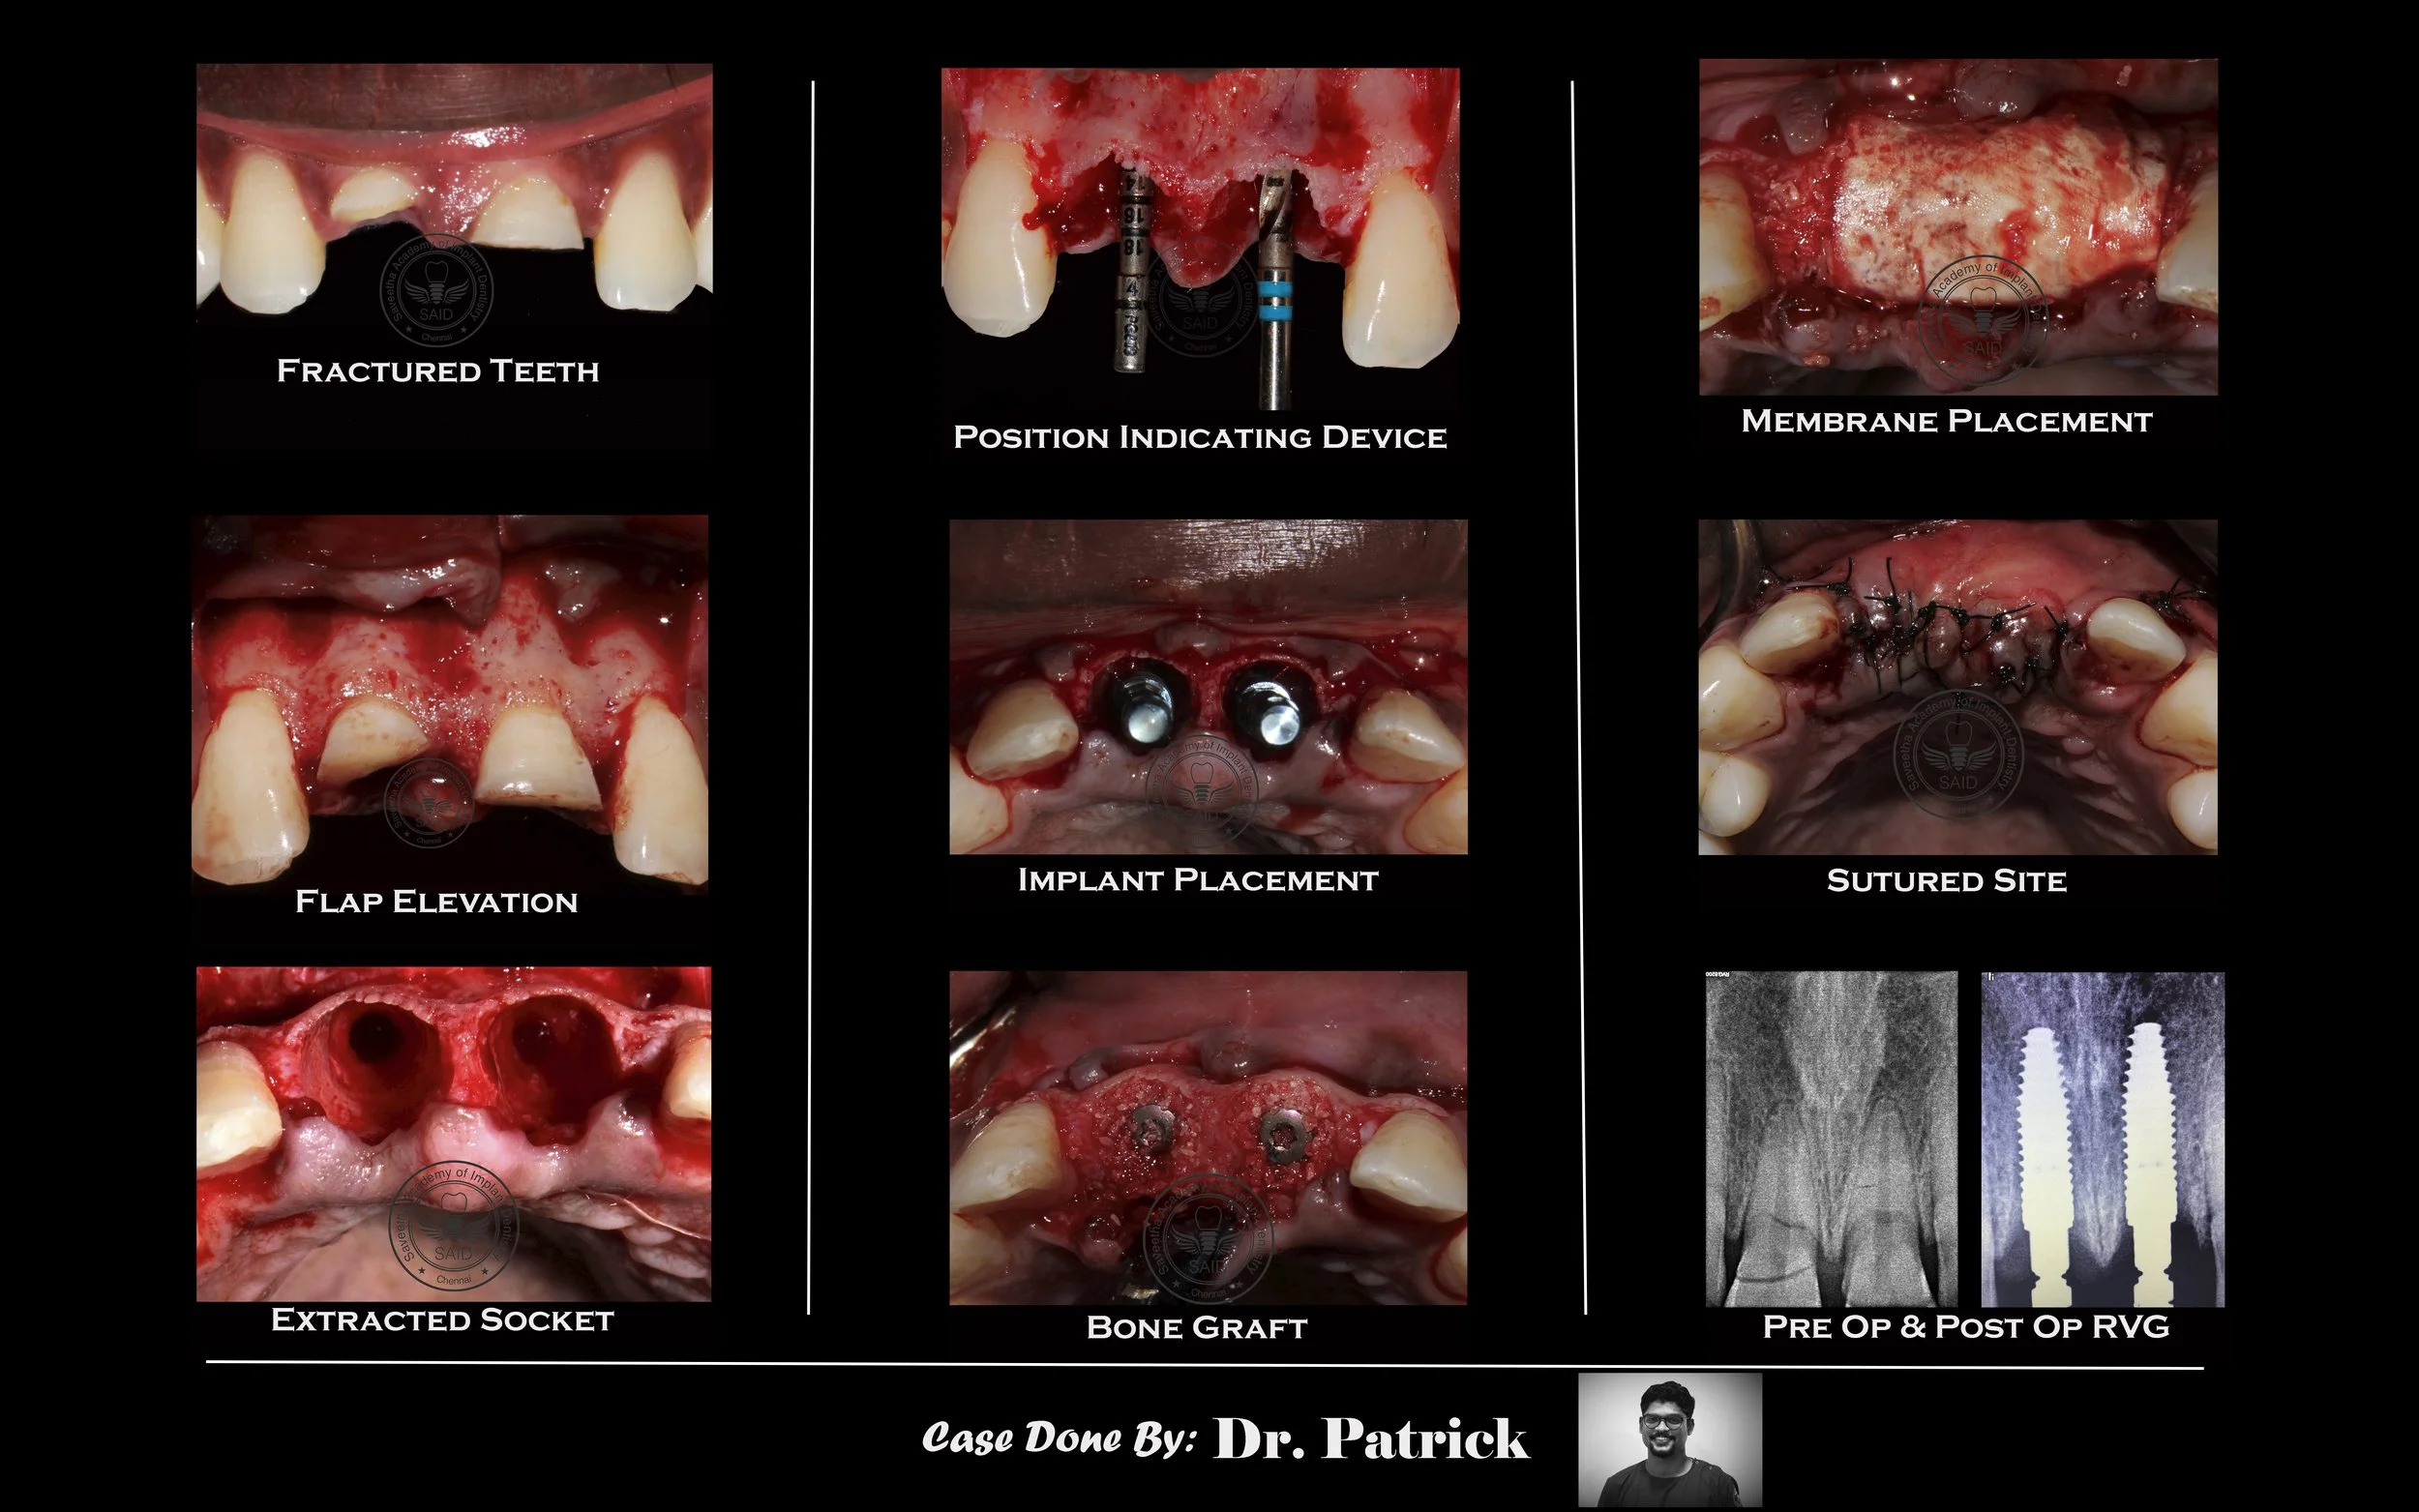

SOCKET PRESERVATION - IMPLANT PLACEMENT

Patient reported having fractured upper front teeth. CBCT evaluation showed defective Incisor. Hence, the teeth was extracted and the socket was preserved using bone grafts material and membrane. After 3 months of adequate healing, Implants were placed.